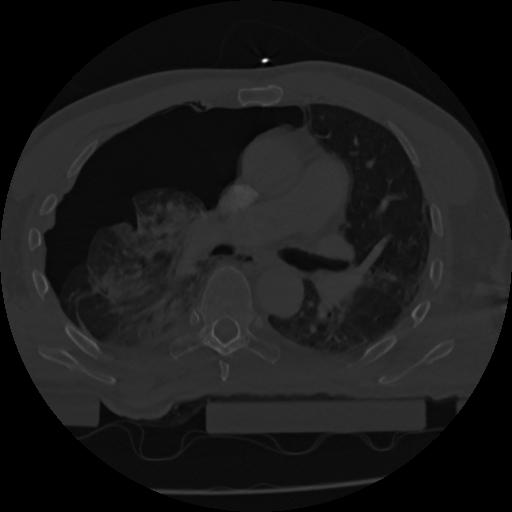

22 ANGIO,CE,Vol,0.5,ANGIO,,